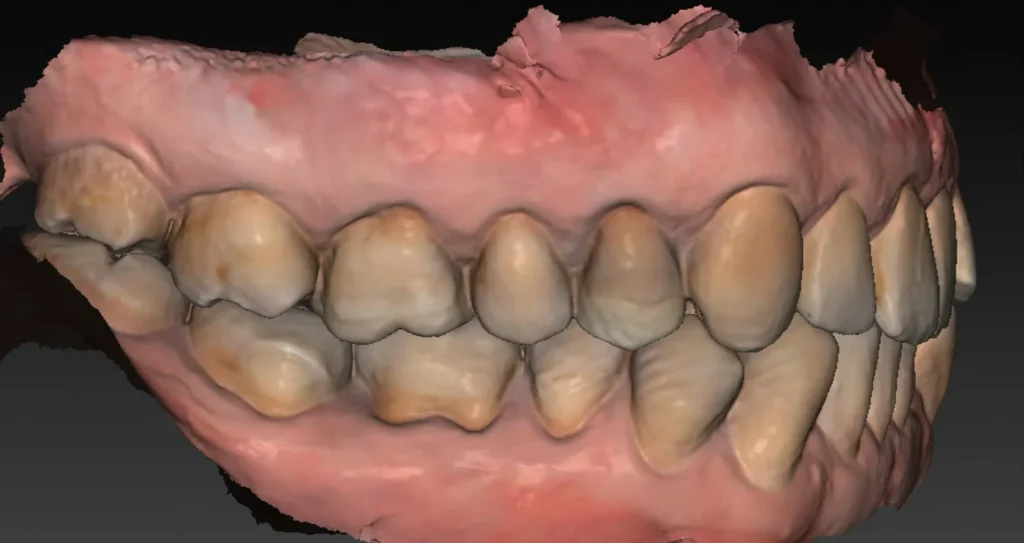

Une empreinte optique est également effectuée. Elle permet :

- de visualiser avec précision le relief gingival et d’identifier les zones nécessitant éventuellement une greffe de gencive ;

- d’évaluer les rapports occlusaux en vue de la future restauration prothétique ;

- d’alimenter la planification numérique en superposant les données optiques au volume osseux issu du Cone Beam.

L’ensemble de ces données permet ensuite de réaliser une planification implantaire précise, fondée sur une analyse tridimensionnelle croisée des tissus durs et mous, et tenant compte des exigences prothétiques.